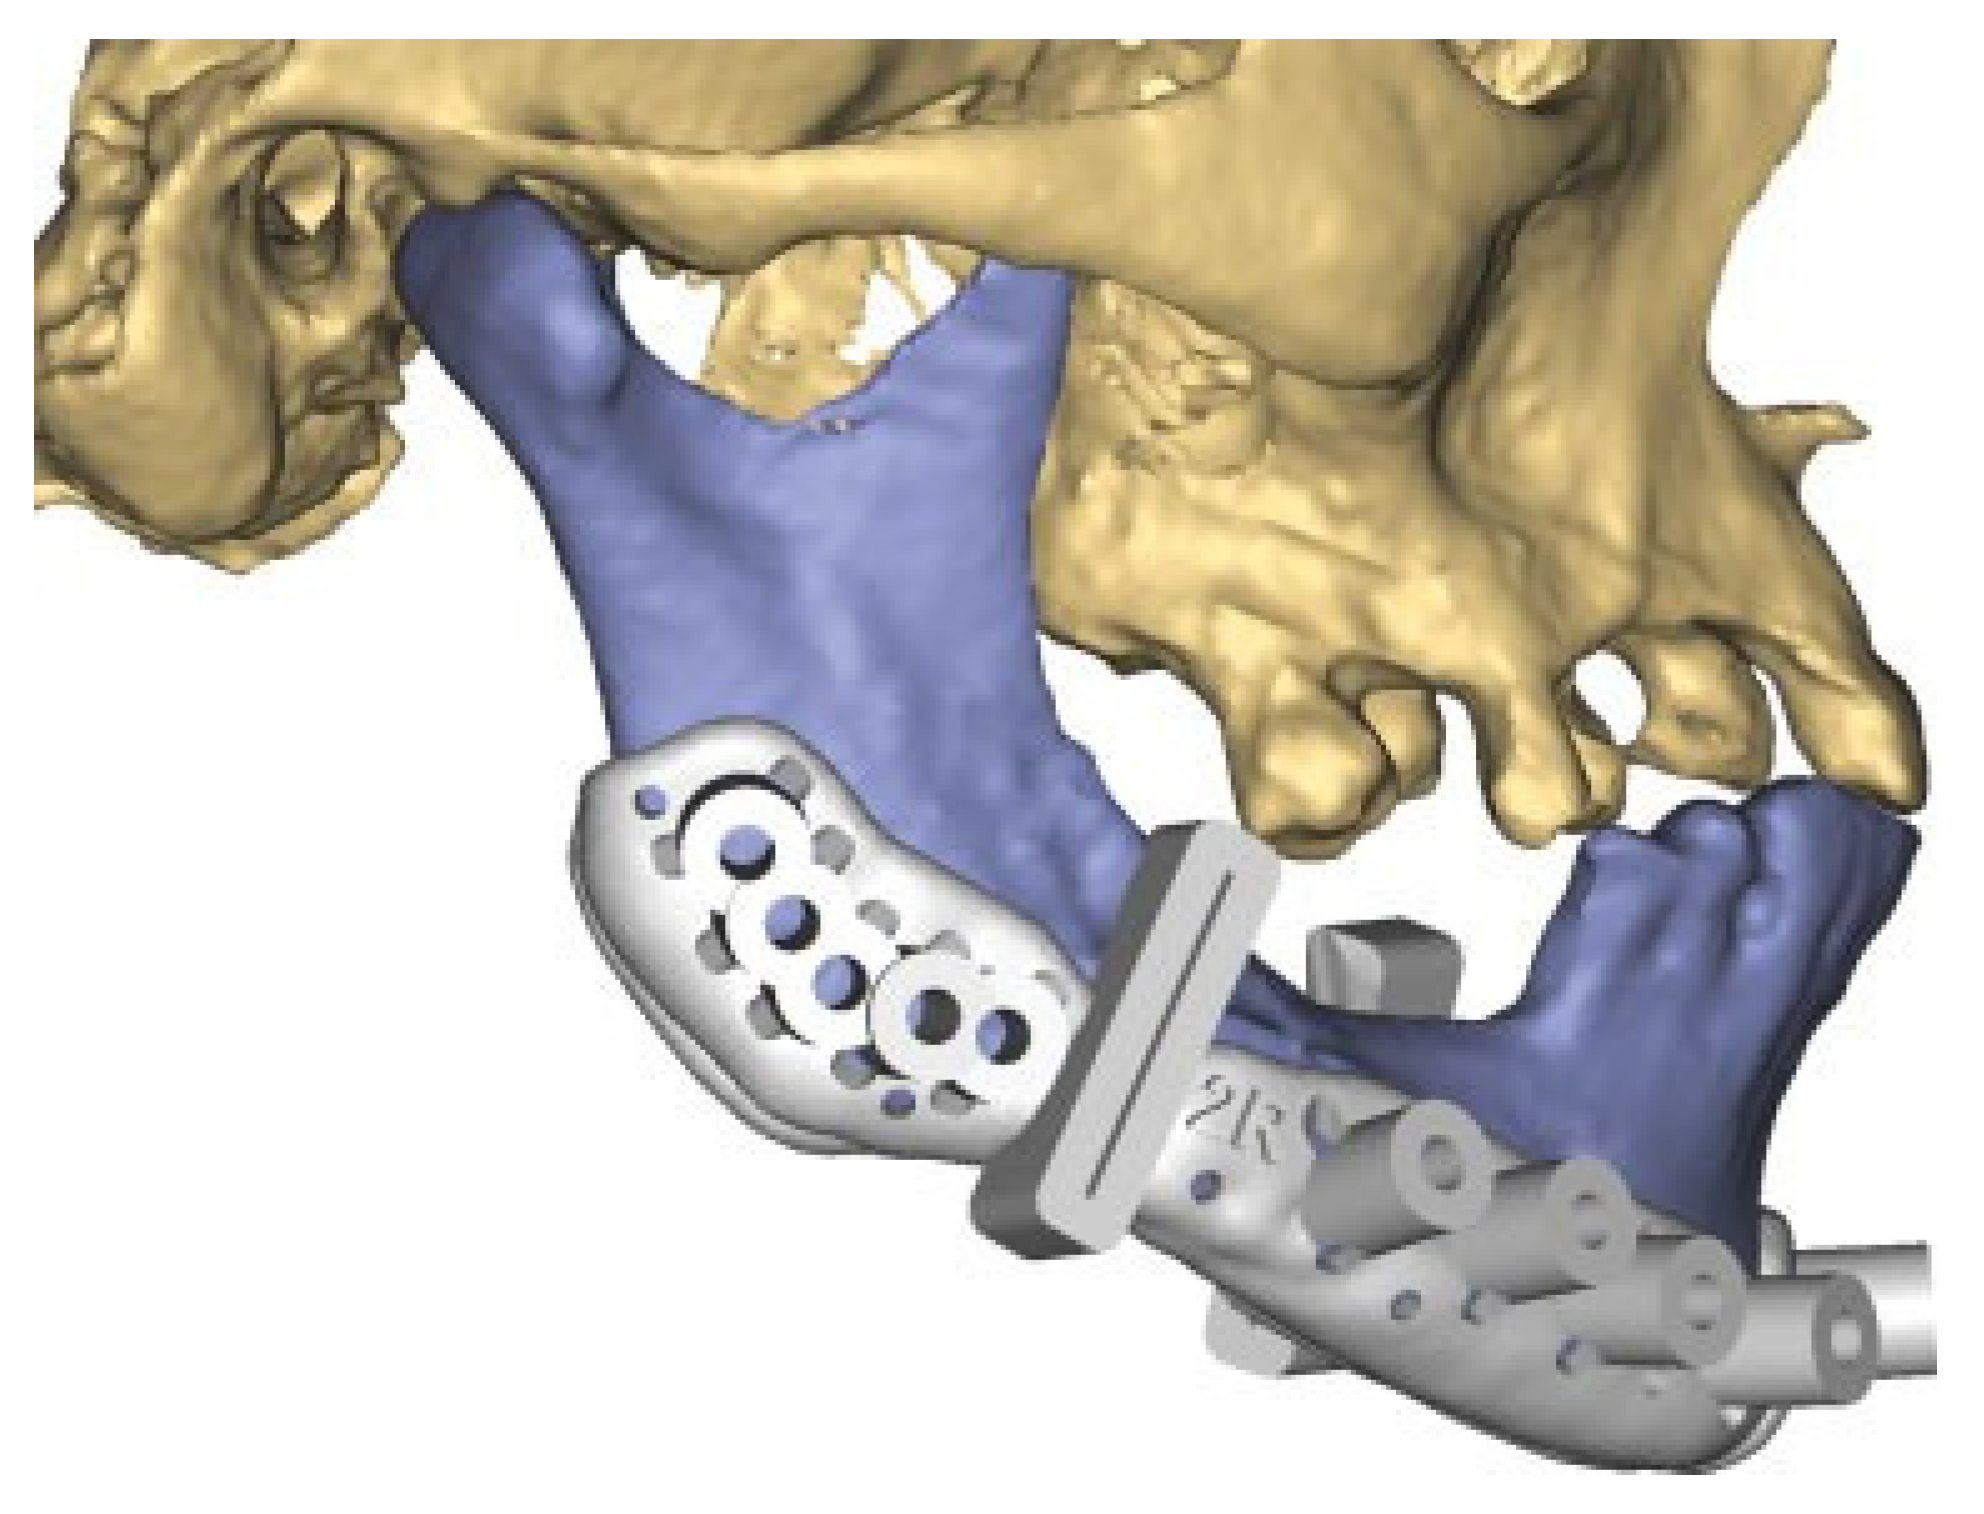

A Patient Specific Implant (PSI), an angle-to-angle mandibular reconstruction plate, was designed and outlined along the mandibular border. Plate holes with locking function for screws were outlined. The dimension of the plate was 2.5 mm thick and 8 mm wide. A total of 18 screw-holes were placed with care taken to avoid the fracture areas, teeth and nerves. (Figure 5) Simultaneously, a combined cutting- and drill guide was produced for osteotomies and drill holes virtually planned in the mandible. (Figure 6) The plate was then manufactured by milling from a titanium block (TRUMATCH® CMF, DePuy Synthes GmbH, Oberdorf, Switzerland) after the surgeon had approved its final form.

Figure 6.

Guide for osteotomies and screw holes (right side).